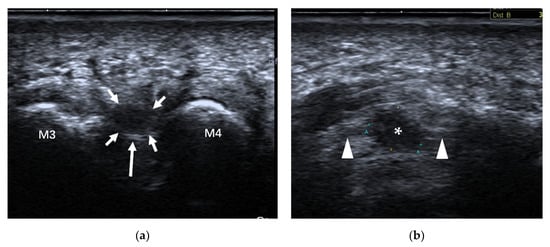

4.2.3. Intermetatarsal Bursitis

| Intermetatarsal bursitis | intermetatarsal spaces between 2nd and 3rd toes | hypoechoic mass with increased vascularity, compressible |